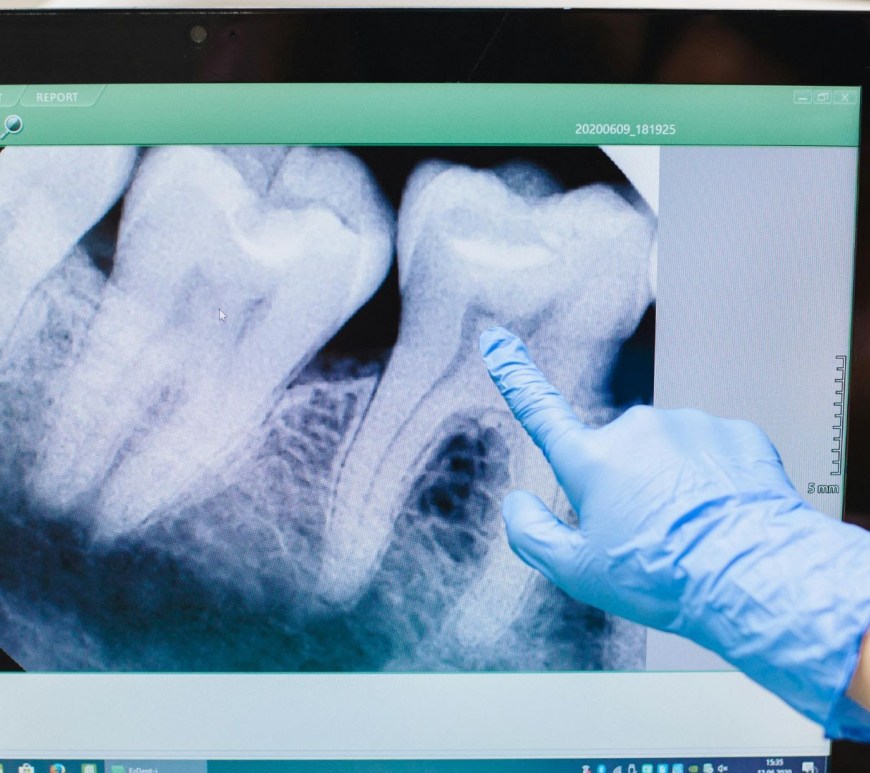

«Cada vez hay más evidencia de que la enfermedad periodontal, una degradación crónica de las encías, puede estar relacionada con un mayor riesgo de sufrir infartos o accidentes cardiovasculares», doctor Carlos Mederos Por Deyanira Vázquez | Reportera Según el doctor Carlos Mederos, Odontólogo especialista en Cirugía, Implantes y Estética Dental del Centro Médico Quirónsalud Plaza Euskadi, mantener una buena salud bucodental no solo previene caries … Continúa leyendo La enfermedad periodontal puede estar relacionada con infartos o accidentes cardiovasculares: Carlos Mederos